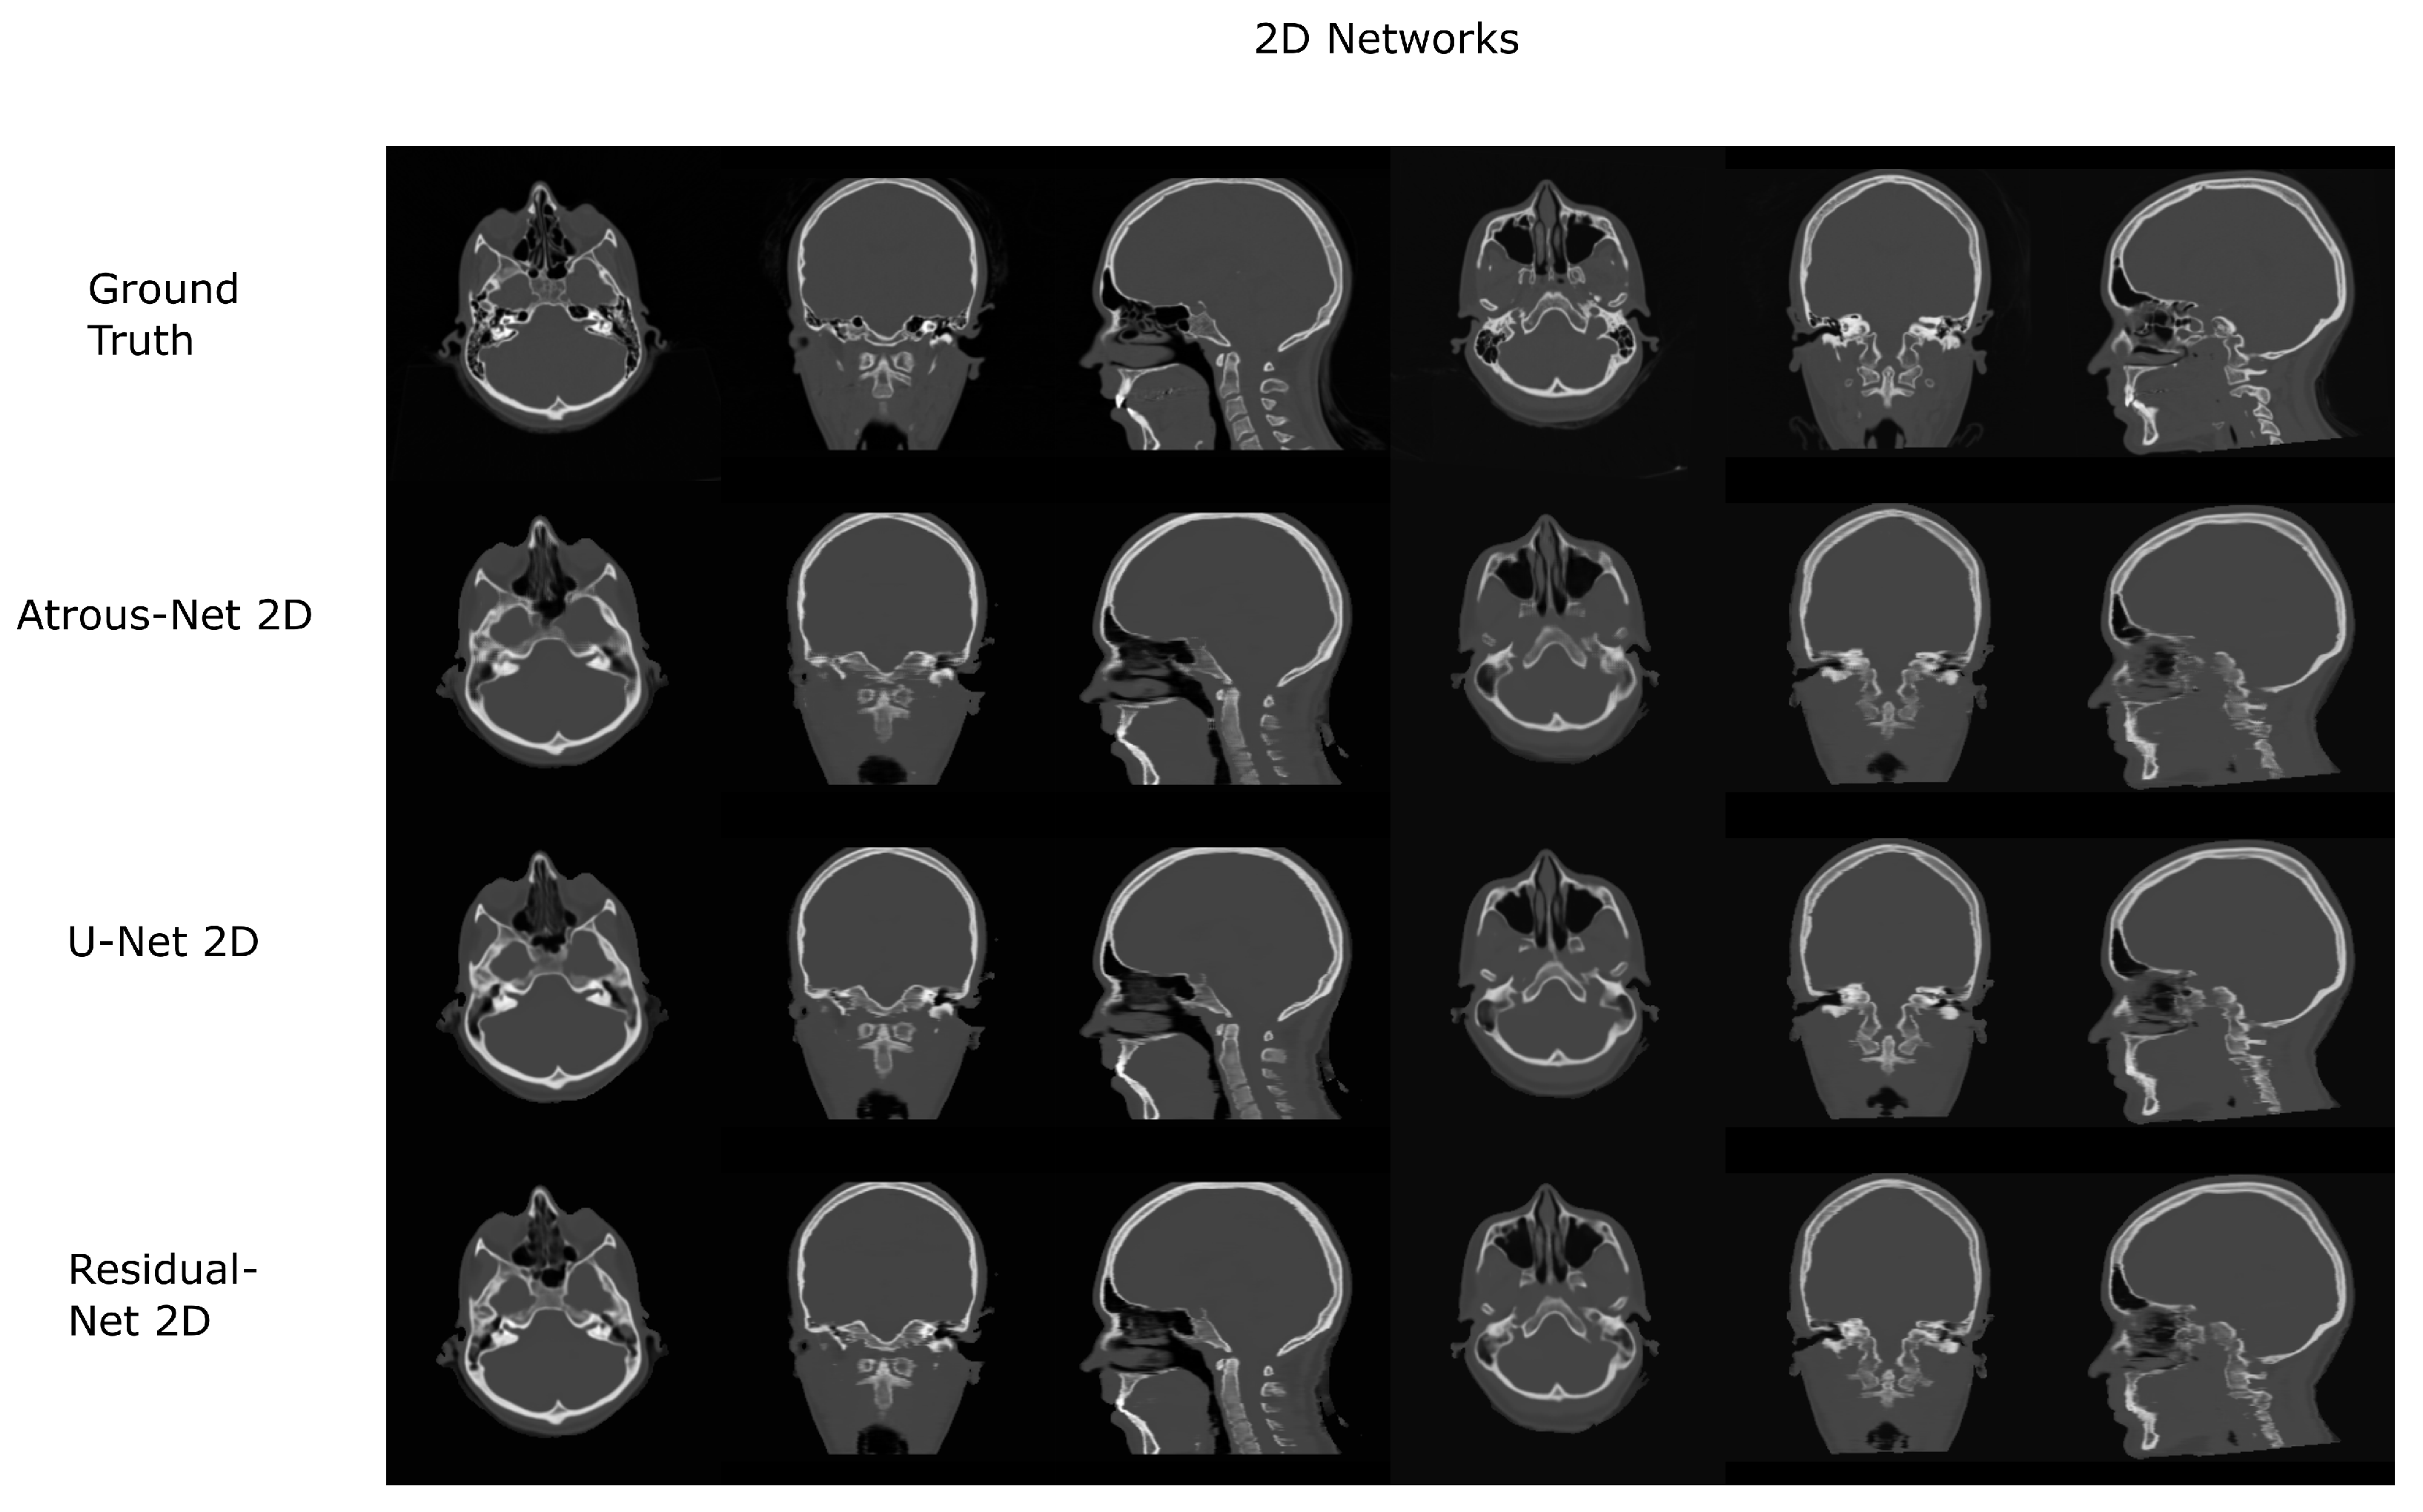

Figure 6.

Head results using 2D networks.

The results for all tissues using the head dataset are depicted in Table 1, Table 2 and Table 3; the results using only the bone voxels are detailed in Table 4, Table 5 and Table 6; the results using only the fat voxels are detailed in Table 7, Table 8 and Table 9; and the results using only the soft-tissue voxels are detailed in Table 10, Table 11 and Table 12. The best performing 2D network for the head dataset was the Residual-net. The results presented a MAE of 99.83 HU, a PSNR of 24.83 and a Pearson Coefficient of 0.931 in all tissues, and a MAE of 326.33 HU, a PSNR of 19.04 and a Pearson Coefficient of 0.826 in bone voxels. The ANOVA test revealed a statistically significant effect of the 2D architectures for MAE results (all tissues: , ; bone: , ) and PSNR results (all tissues: = 99.3, ; bone: = 85.6, ). A paired t-test was used to compare the Residual-net to the other networks reporting also statistically significant differences in the MAE and in the PSNR (Table 13). Using 2D convolutions, the Atrous-net and the U-net performed 5% and 18% worse than the residual-net, respectively. Moreover, the U-net network was clearly behind the other networks using 2D convolutions. Nevertheless, the U-net in 3D-16 obtained a MAE of 89.54 HU, a PSNR of 25.69 and a Pearson Coefficient of 0.943 in all tissues, and a MAE of 289.10 HU, a PSNR of 20.05 and a Pearson Coefficient of 0.861 in bone voxels, which were the best results for the head dataset. The ANOVA test also reported a statistically significant effect of the 3D networks for the MAE (all tissues: ; bone , ) and the PSNR (all tissues: , ; bone: , ). The post hoc paired t-test that is depicted in Table 14 also reported statistically significant differences in the MAE and PSNR after comparing each architecture. Summarizing, the results using 3D convolutions from the U-net were 17% and 10% better than those of the Atrous-net and Residual-net, respectively. Visual result examples of head pseudo-CTs are depicted in Figure 6 and Figure 7. Table 15 shows the time needed to synthesize a whole head volume using the different architectures.

According to the results of the current work, there is no preferred network for every problem. Thus, the results depend on the specific anatomy defining the problem and the MRI sequence that is used. As shown in Section 4. Results, if the anatomy is similar to a head with complex bone structures and geometries, 2D schemes generate aliasing and artifacts across bone structures. Instead, 3D schemes and reconstructions with stride 16 provide bones with smooth boundaries, which is translated into a significant reduction of the error. Moreover, the best architecture to achieve the best detail in a head pseudo-CT is the 3D U-net (). When using 3D architectures, the input of the network is usually a 3D patch due to GPU memory limitations. 3D patches only depict a part of the anatomy. Therefore, they provide limited contextual information. In this case, the progressive spatial reduction and up-sampling of the feature maps are probably the best option, as it occurs in the U-net.